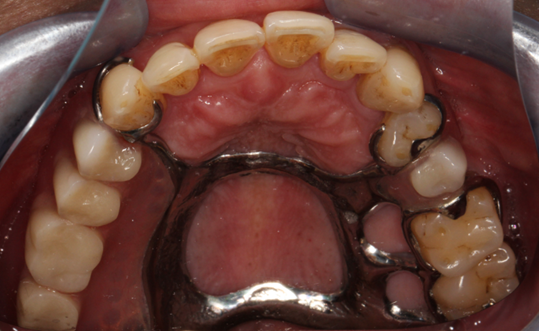

假牙,江(口)湖(腔)人称义齿,就是牙齿缺损或者缺失以后模拟天然牙的形态和功能做的修复体。根据能否由患者自行摘戴,可以将其分为活动义齿和固定义齿。活动义齿就是可以随时摘戴,随意取出的假牙,不能取出的就是固定义齿。活动义齿根据还有没有余留的天然牙齿,分为可摘局部义齿和全口义齿。今天我们就来看看还余留部分天然牙的可摘局部义齿的使用注意事项。

图片1.png